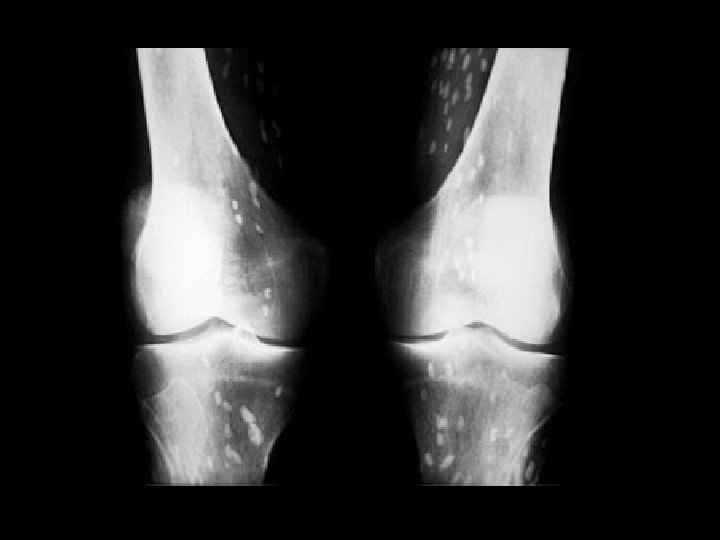

Rickets • Findings: – Cupped and frayed metaphyses – Wide physes (increased osteoid) – Long bone bowing – Decreased bone density • ddx: – NONE! – This is an Aunt Minnie!